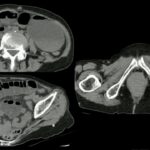

A obstrução intestinal ocorre quando há uma interrupção no fluxo natural do intestino. Quando comemos, a comida passa pela boca, esôfago, estômago e intestino até ser eliminada nas fezes. Se houver obstrução no meio do caminho, o alimento fica preso em uma parte e não consegue seguir o percurso natural, causando a obstrução intestinal.

A obstrução intestinal pode ser mecânica, quando há uma obstrução física por algo que está entupindo o intestino, como uma hérnia, um tumor ou bridas intestinais (tecido fibroso que gruda as alças do intestino). Também pode ser funcional, quando o intestino perde a capacidade de se movimentar e empurrar o alimento.